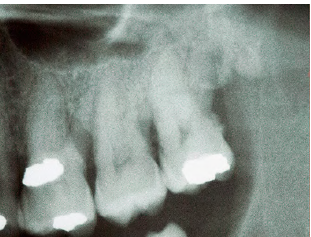

We can see the corresponding radiograph;

-although the radiograph suggests generalized bone loss, there is a lot of calculus on

the distal of #16 > it makes sense that this is a pyogenic granuloma